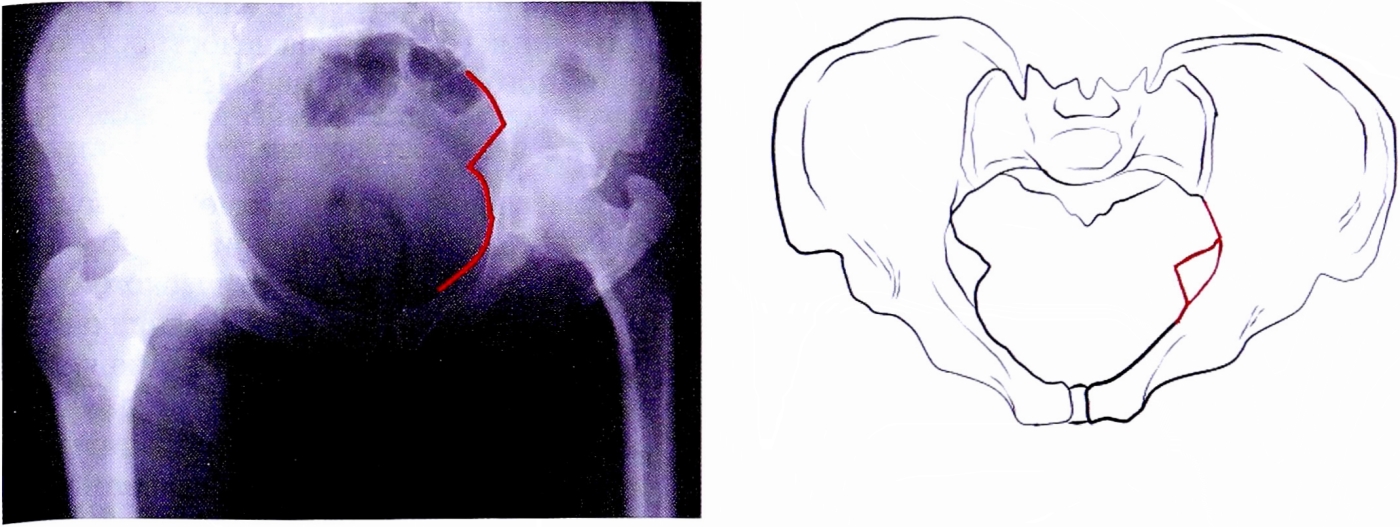

- Контур задней стенки вертлужной впадины (задний край впадины) соответствует переходу самой стенки в хрящевую губу (рис. 5).

Рис. 5. Контуры задней стенки на рентгенограмме и на схематическом изображении таза.

Fig. 5. Posterior wall brim on AP pelvic X-ray and on schematic pelvis.